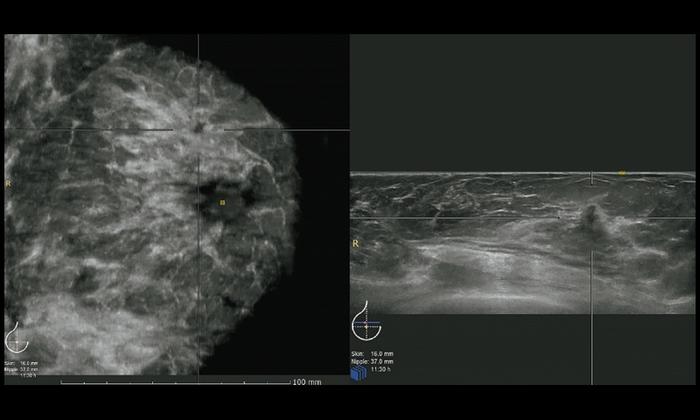

Пациентка по имени М., 39 лет. В ходе УЗИ с автоматическим объемным сканированием (ABVS) была обнаружена опухоль в правой молочной железе на 12.30 условной цифре циферблата, расположенная в 41 мм от соска и на глубине 16 мм. Образование демонстрировало пониженную эхогенность, вертикально ориентированное с нечеткими контурами и размером приблизительно 0,6 см, с акустической тенью и увеличенной эхогенностью окружающих тканей (десмопластическая зона). При коронарной проекции трехмерной реконструкции замечена лучистость контура. Заключение: подозрение на рак правой молочной железы, BI-RADS 4. Пациентка была направлена на маммографию с томосинтезом, в результате которой в верхненаружном квадранте выявлен узел неправильной формы с нечеткими тяжистыми контурами размером 1,0 х 0,8 см. На границе внутренних квадрантов обнаружены еще два образования с тяжистыми контурами до 0,4 см, а медиальнее — еще один аналогичный участок размером 0,6 х 0,3 см. При МР-МГ зафиксирован мультицентричный рост опухоли: участки патологической васкуляризации показывают пик накопления контрастного вещества в первые 2 минуты контрастирования с последующим быстрым выводом контраста. Заключение: рак правой молочной железы I стадии (люминальный A, ER+, PgR+, HER2 негативный, Ki-67 15%). У пациентки было проведено комбинированное лечение, включающее радикальную резекцию, лучевую и гормональную терапию. На момент составления статьи пациентка наблюдается уже в течение 5 лет без признаков прогрессирования.

Микрокальцинаты часто обнаруживают при раке молочной железы, встречающемся в 42% случаев, и являются хорошо видимыми на рентгеновской маммографии. Этот метод обладает высокой предсказательной возможностью для определения распространенности внутрипротоковых опухолей. Рентгеновская дуктография считается ведущим методом диагностики внутрипротокового рака молочной железы благодаря выявлению микрокальцинатов, которые могут указывать на злокачественные процессы. Косвенные признаки непальпируемого рака Включают микрокальцинаты, которые лучше регистрируются при маммографии.

Поскольку микрокальцинаты являются одним из характерных признаков злокачественного процесса, их обнаружение играет важную роль. При использовании высокоразрешающего ультразвукового оборудования с правильно настроенными датчиками можно идентифицировать мелкие эхогенные точки внутри образования, сопоставимые с маммографическими изображениями кальцинатов. Как правило, маленькие кальцинаты не создают акустической тени. На УЗИ молочных желез трудно различить микрокальцинаты на фоне эхогенной железистой ткани или тканей с высоким количеством отражающих поверхностей.